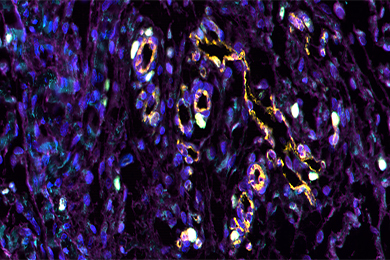

病理图像分析系统是一门先进的病理诊断系统,采用先进的图像处理技术与高精度硬件配置,从系统信号的获取、测量、处理到打印输出全部实现彩色化、自动化、智能化,具有操作简便、图像处理功能强、图像分析智能化、图像清晰度高、图文报告打印快捷、数据库管理功能强大等优点。